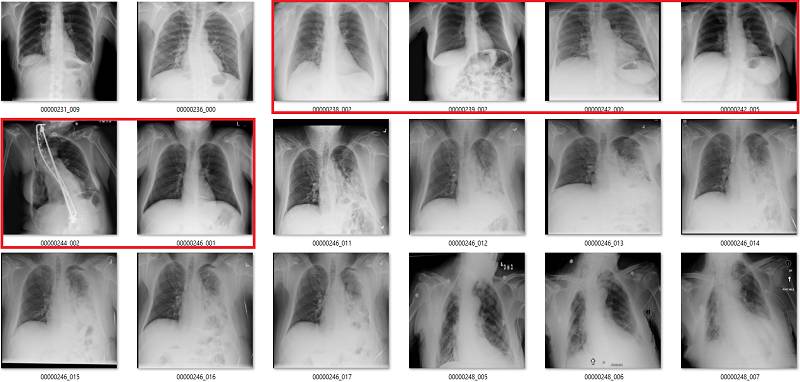

渗出(Effusion)

在该案例中,蓝色的标签表示它们存在显著性的肺部疾病。

渗出(effusion)表示在肺部周围空间有积液。造成该病变的原因非常多,但主要原因分为由胸膜和肺部疾病引起的积液。

我并不清楚什么确定或代表了显著性肺部疾病中有积液存在。在很多情况下,甚至直观地识别这些积液都是不可能的,只不过我们知道积液会存在,所以我们也就这样描述它了。上图最后三个肺部影像就是一个非常好的例子,在我看来,这些病例的主要病理还是固结(consolidation)。

我可以看到识别较小和分离的胸腔积液的价值。上图中约有 6 张影像是这样的情况,包括第一张和第三张。没有肺部疾病来表明积液的成因,这令标签「积液」越发突兀。

我还可以看到识别较大积液的好处,它们可能需要我们的介入进行治疗,如使用器械将它们排出。第 10 张图就正好是这样的案例。所以其实我并不太了解标签的含义,因为不是基于临床实践的指导思想并不是很有用。

气胸(Pneumothorax)

气胸是指在肺部周围的胸膜腔空间有气体。这可能导致肺部瘫痪,因此它是非常严重的病变。但实际上,气胸在 X 光影像上非常微小,经常会被人忽略掉。

初次看来,标签似乎非常有效。在这 18 个样本中,只有用橙色标出的那张影像有点问题,这也可能是因为我没在诊断环境下查看肺部影像的原因。

但是绿框也有点问题,因为这些病人已经使用胸腔引流治疗过气胸。因此,现在有以下两个问题:

这并不是医学上重要的问题,我们希望避免气胸未被诊断出的错误,而这些图像标签确实没有犯这种错误。

如果很多影像都通过胸腔引流治疗,AI 系统将会学习识别胸腔引流而不是气胸。模型训练时的大多数图像样本批量完全可能包含有胸腔引流的气胸。

纤维化

我们已经看到,纤维化的标注准确率非常低。在这些影像中,红框是不正确的标签,橙框是我不确定的标签。在胸腔积液和固结中可能也会出现纤维化,但这些是影像无法告诉我们的。

真正类

绿色是真正类,其它的是错误的标签。

真负类

前 18 张有 1 到 2 个有争议,后面 18 张中红框都是错误的。

假正类

红色的都是错的,数据集中也出现了旋转和扭曲等异常情况(用红色问号标记)。

假负类

红色部分为严重错误标注。